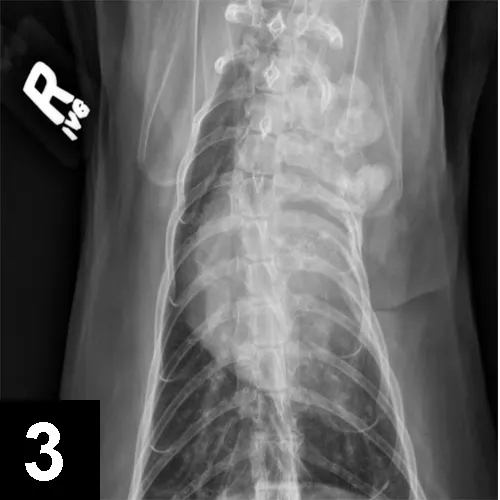

Thoracic VD x-ray of a cat showing proliferation and loss of detail of the cranial left rib cage.

FIGURE 3

VD thoracic radiograph of a cat with left-sided Horner syndrome showing a sarcoma affecting the first 4 ribs and cranial thorax on the left, impacting preganglionic neurons.